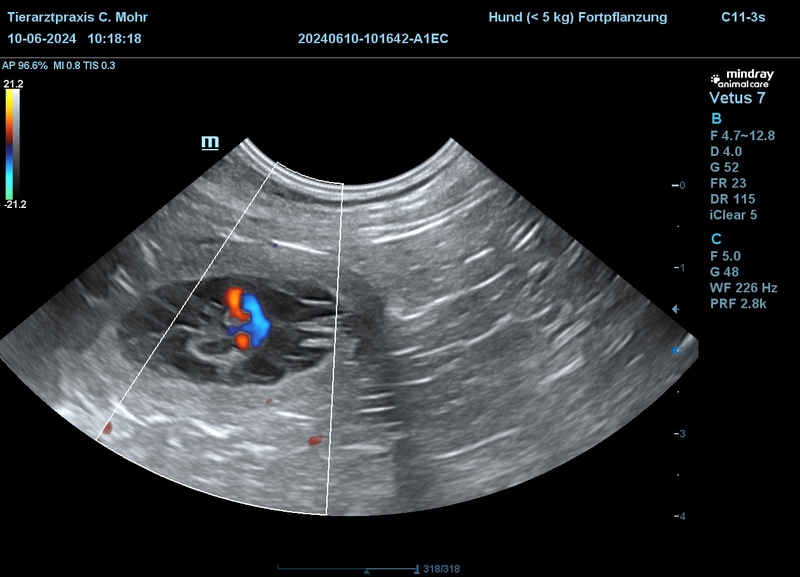

Gina hatte sich relativ schnell auf ihren Wurf vorbereitet und am Sonntag dem 14.07.2024 ihre Welpen problemlos zur Welt gebracht.